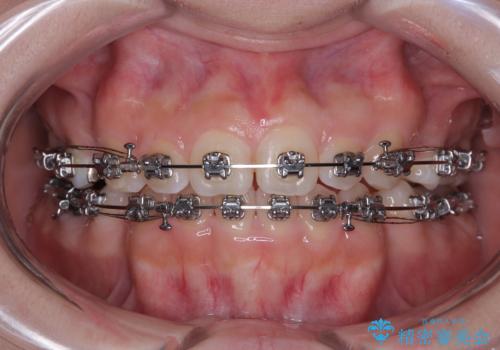

- 矯正装置

- メタルブラケット